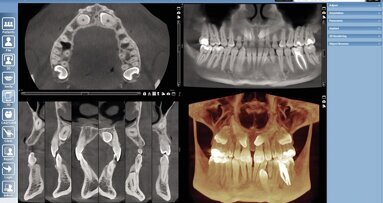

Second Opinion is the only chairside AI software with global regulatory clearance to assist dentists in the detection of numerous common conditions on bitewing, periapical and panoramic radiographs of permanent dentition in patients as young as 12 years old. For Romexis users, the Second Opinion software will provide AI evaluation of 2D intra-oral radiographic images directly within the Romexis platform, facilitating streamlined patient communication, enhanced diagnostic capabilities and a higher standard of dental care delivery.

HELSINKI, Finland/LOS ANGELES, US: Pearl and Planmeca recently announced plans to integrate Pearl’s Second Opinion, an artificial intelligence (AI) diagnostic tool that assists in dental radiography, within the Planmeca Romexis imaging software platform. Pearl is a global leader in dental AI solutions, and Planmeca is the world’s largest privately owned dental equipment manufacturer.